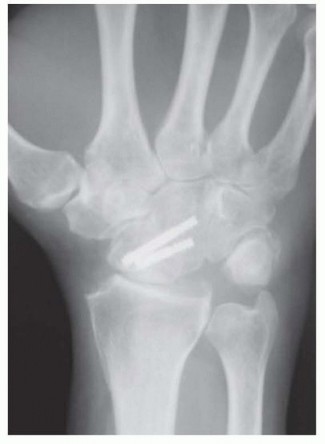

RADIOCARPAL (RADIOLUNATE) ARTHRODESIS

TECH FIG 6 • A,B. Preoperative AP and lateral radiographs. C,D. Postoperative AP and lateral radiographs following radiocarpal arthrodesis. Under fluoroscopy, correct any preoperative VISI or DISI deformity.A Kirschner wire inserted into the dorsal lunate may be used as a joystick to effect correction.Stabilize the lunate in the reduced position with provisional Kirschner wires from the radius into the lunate.Harvest bone graft from the distal radius or iliac crest and pack the graft tightly into the palmar radiolunate joint.Secure the lunate to the radius with Kirschner wires, headless screws, staples, or small blade plates. Pack the remaining bone graft into the dorsal radiolunate joint.Perform a routine closure and apply a splint.The previously described technique is taken from published data.14,278. Capitolunate ArthrodesisMake a dorsal incision from base of second metacarpal to Lister tubercle.Use the third and fourth extensor interval as described earlier.Perform an inverted “T” capsulotomy to visualize the scapholunate and capitolunate joints. Perform a limited styloidectomy (˜3mm) and excise the proximal pole of scaphoid.Stabilize distal scaphoid to capitate with a Kirschner wire. Alternatively, the entire scaphoid can be excised.Denude the capitolunate articulation.Harvest bone graft from distal radius or iliac crest and pack it into this prepared joint.Tricortical iliac crest graft allows maintenance of carpal height.Assure capitolunate alignment with a Kirschner wire as described earlier for CHLT fusion.Place a guidewire followed by headless screw into proximal ulnar corner of lunate as described earlier for CHLT fusion.Take wrist through a range of motion to be certain a mechanical block is not present. Perform a standard closure and apply a splint.The previously described technique is taken from published data.12,15P.989